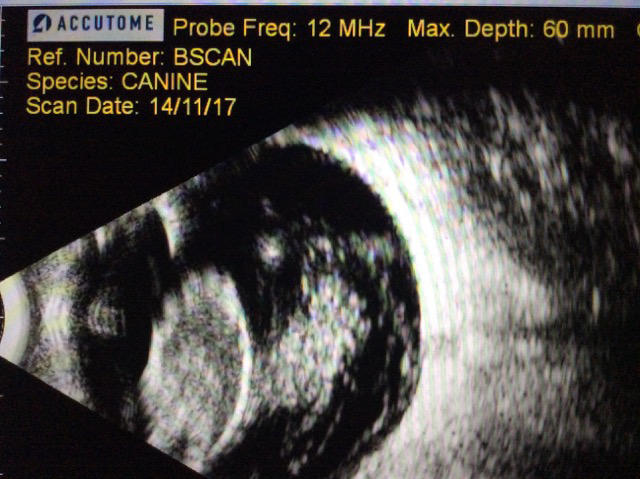

- En la ecografía se aprecia también que tiene una degeneración vítrea en ambos ojos sin otras alteraciones adicionales

- En la exploración se aprecia una luxación posterior de cristalino en los dos ojos con presencia de catarata hipermadura